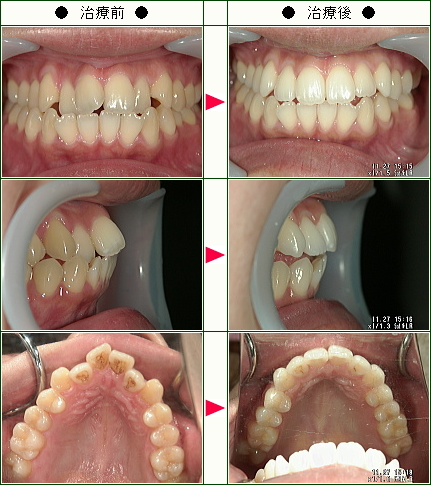

☆歯のデコボコ矯正症例(T・A様 25歳 女性)